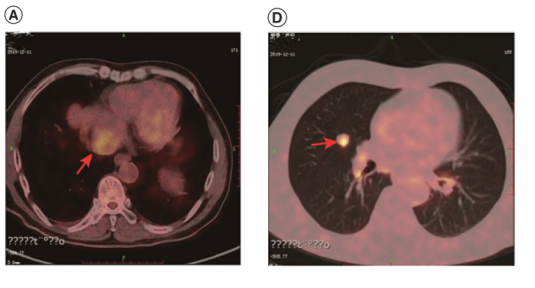

约6个月后,PET-CT扫描显示下腔静脉-右心房(IVC-RA)连接处有肿瘤血栓(40×36mm);双肺多发转移结节(最大直径12毫米),肺、纵隔淋巴结多发转移。

在无明显症状报告的情况下,患者ECOG评分为1分,肝功能Child-Pugh A级。于2020年1月开始接受信迪利单抗(每3周静脉滴注200 mg)联合索拉非尼(400 mg口服,每日2次)治疗。